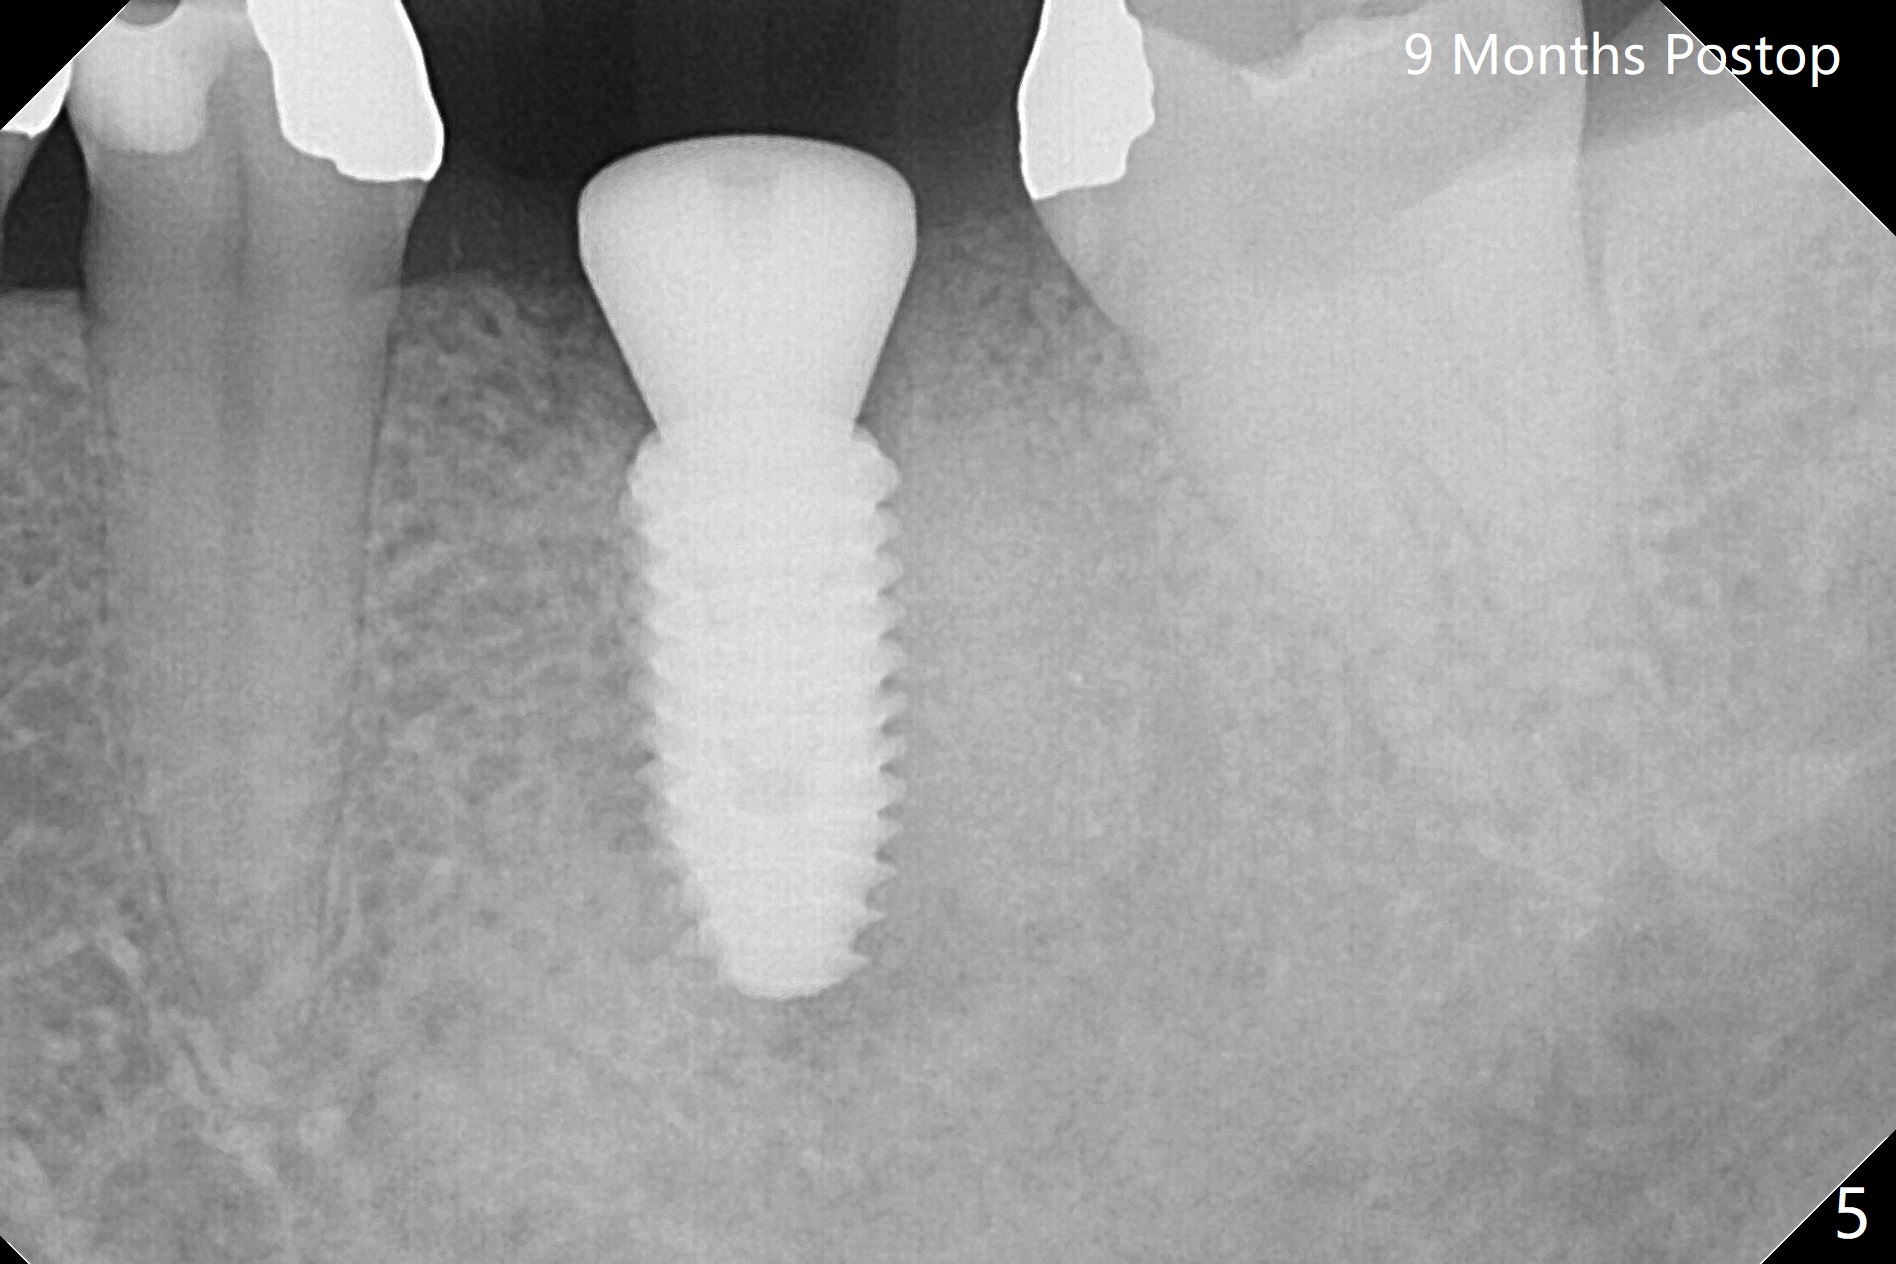

The ridge at #19 is slightly atrophic 5 months post socket preservation (Fig.1). The bone is long enough to hold a 11.5 mm long implant. There is no difficulty in inserting the corresponding drill (4.5x11.5 mm) into the metal sleeve, but the lower right posterior teeth prevent the implant handpiece from going downward completely when the handpiece accesses lingually. Because of the extra manipulation, a 5x10 mm implant achieves insertion torque of ~ 20 Ncm (Fig.2). The implant seems to be seated in the middle of the ridge (Fig.3). The bone density mesial to the implant increases 5 months postop (Fig.4), whereas that distal to the implant remains low 9 months postop (Fig.5). Bitewings taken 2.5 months post cementation (1 year postop, Fig.6,7) show subcrestal placement of the implant (advantage of guided surgery). The implant appears to be well protected; the crestal bone seems to cover the implant plateau. There will be little chance of thread exposure over years of use. The trabecular pattern around the implant is similar to that around the roots of the tooth #30 one year 7 months post cementation (2 years 4 months postop, Fig.8).